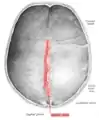

![]() Human adult skull from above. Sagittal suture labeled at center. | |

The sagittal suture, also known as the interparietal suture and the sutura interparietalis, is a dense, fibrous connective tissue joint between the two parietal bones of the skull. The term is derived from the Latin word sagitta, meaning arrow.

The sagittal suture is formed from the fibrous connective tissue joint between the two parietal bones of the skull.[1] It has a varied and irregular shape which arises during development.[1] The pattern is different between the inside and the outside.[1]

Two anatomical landmarks are found on the sagittal suture: the bregma, and the vertex of the skull. The bregma is formed by the intersection of the sagittal and coronal sutures. The vertex is the highest point on the skull and is often near the midpoint of the sagittal suture.